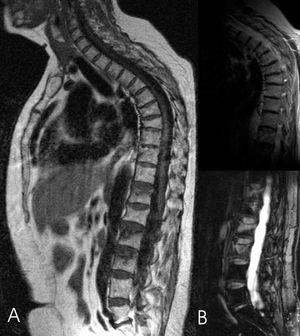

En estos pacientes se realiza un estudio mediante resonancia magnética (RM), empleando secuencias sagitales potenciadas en T1 y secuencias T2 con supresión grasa (STIR).

En las secuencias potenciadas en T1, la fractura vertebral reciente se manifiesta con una disminución de la señal de resonancia. En las secuencias potenciadas en T2 con supresión grasa o STIR, la manifestación es una hiperseñal, fácilmente identificable por la supresión grasa; estos cambios de señal traducen la presencia de edema y se correlacionan con un proceso agudo, susceptible de ser tratado mediante vertebroplastia (fig. 1).

Figura 1. A: resonancia magnética sagital de columna con secuencia espín eco potenciada en T1: las fracturas agudas en L3, L2, T12 que presentan disminución de la intensidad de señal, fracturas vertebrales consolidadas, sin edema, en territorio dorsal medio. B: resonancia magnética sagital con secuencia espín eco potenciada en T2 con supresión grasa, hiperseñal en las vértebras con fractura reciente.